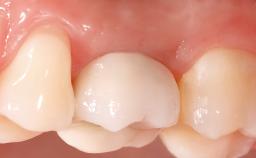

In February 2002, a 31-year-old non-smoking male patient was referred by his dentist after the fracture of the crown of the maxillary right second premolar, tooth 15. The fracture line was located apically to the gingival margin, particularly on the palatal side. Radiographic examination revealed the presence of a previous endodontic treatment with a non-ideal apical seal. There were no signs of periapical osteolysis. The level of the interproximal bone was normal. The patient’s medical history did not reveal any significant findings and he was in good general health.